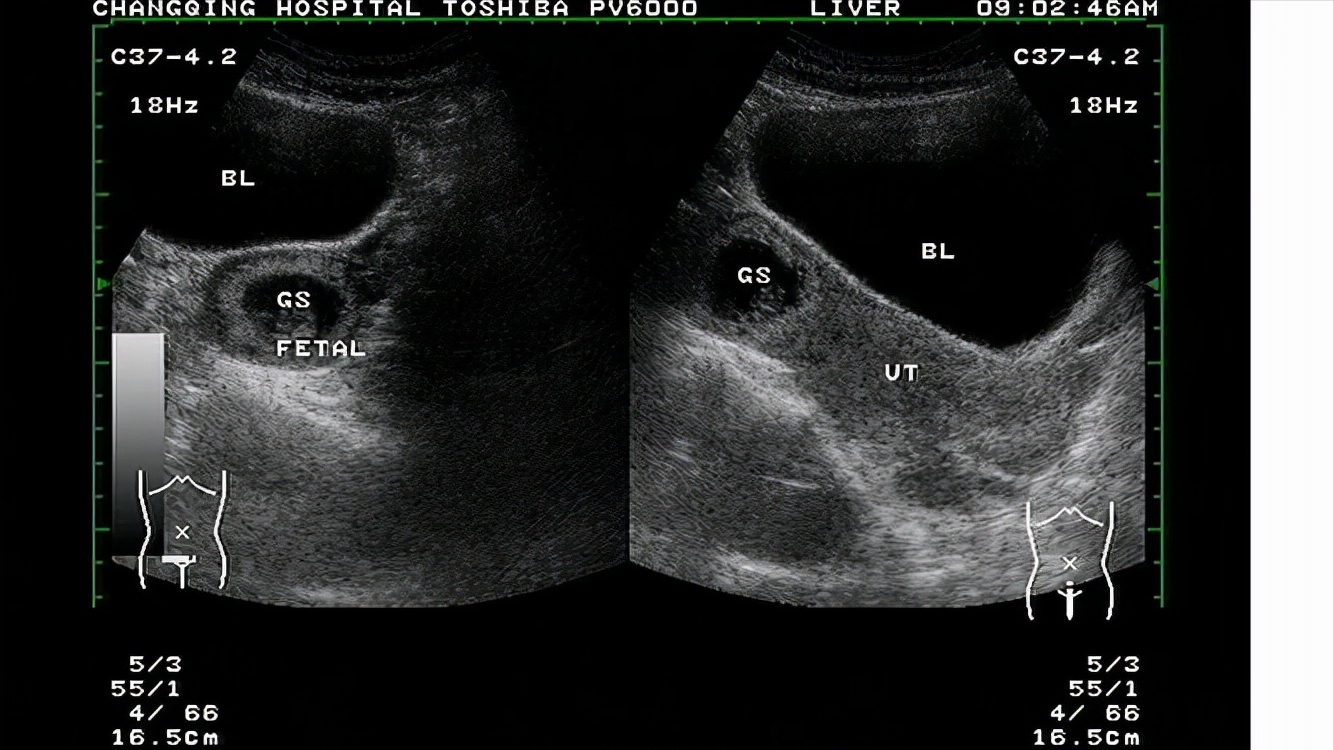

就算能够怀胎十月,但宫外孕的孩子没有得到足够多的营养,会不会影响智力的发育呢,当前情况已经容不得医生多想,于是便给产妇做了一次B超,结果很快便出来了,

根据检测结果显示,赵正芹的肚子里还有一位女孩,女孩此刻安安稳稳地蜷缩在母亲子宫里。

这可让医生彻底傻眼了,刚才她可是亲手检查的,赵正芹的子宫内什么都没有,可是机器检测的仪器却显示得清清楚楚明明白白,这到底是怎么回事?

而赵正芹却拥有两个子宫,分别位于肚子的左右两侧,一左一右两个子宫,分别养育了一位男孩和一位女孩。

一个月前,位于左侧的男孩顺利出生,但是在男孩出生后,右侧的子宫丝毫没有生产的迹象,子宫颈也紧紧闭合。

时隔一个月,在右侧子宫里的小女孩才终于有了生产的迹象,而这也是赵正芹肚子久久不能恢复原状的真正原因。